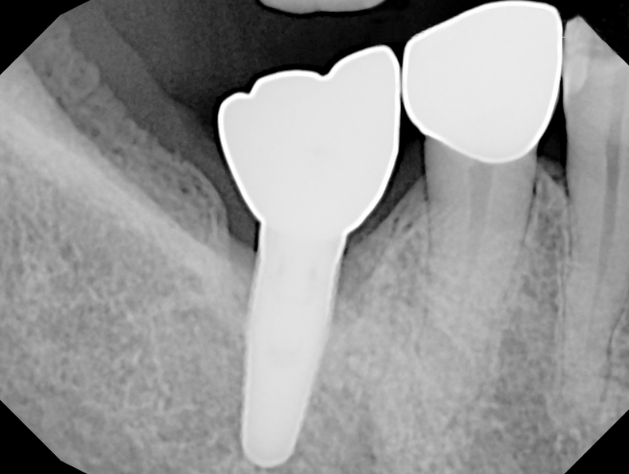

The LAPIP protocol offers a minimally invasive, laser-based method for treating peri-implantitis—the inflammation and bone loss that threatens the stability of dental implants. Using the same PerioLase® MVP-7™ technology as LANAP, LAPIP precisely targets infected tissue and harmful bacteria surrounding the implant while protecting healthy gum and bone. This allows the body to naturally rebuild lost support and helps save implants that would otherwise be at risk of failure. With no cutting or sutures required, LAPIP provides a gentle, highly effective alternative to traditional peri-implant surgery.

LAPIP™ (Laser-Assisted Peri-Implant Procedure) is a minimally invasive laser treatment designed to save ailing or failing dental implants caused by peri-implantitis. Using the PerioLase® MVP-7™ Nd:YAG laser, the protocol targets inflamed, infected tissue and titanium corrosion contaminants while preserving healthy gums and bone. This tissue-sparing approach promotes bone regeneration around the implant and offers a more comfortable treatment with less bleeding, swelling, and downtime than traditional surgery.

Traditional gum and implant surgery often requires cutting into the tissue, lifting flaps, and stitching the area closed afterward. These methods can increase trauma, bleeding, swelling, and longer recovery times. LANAP and LAPIP eliminate the need for scalpels or sutures by using the PerioLase® MVP-7™ laser to selectively remove infection while protecting healthy gum and bone—whether around natural teeth or dental implants.